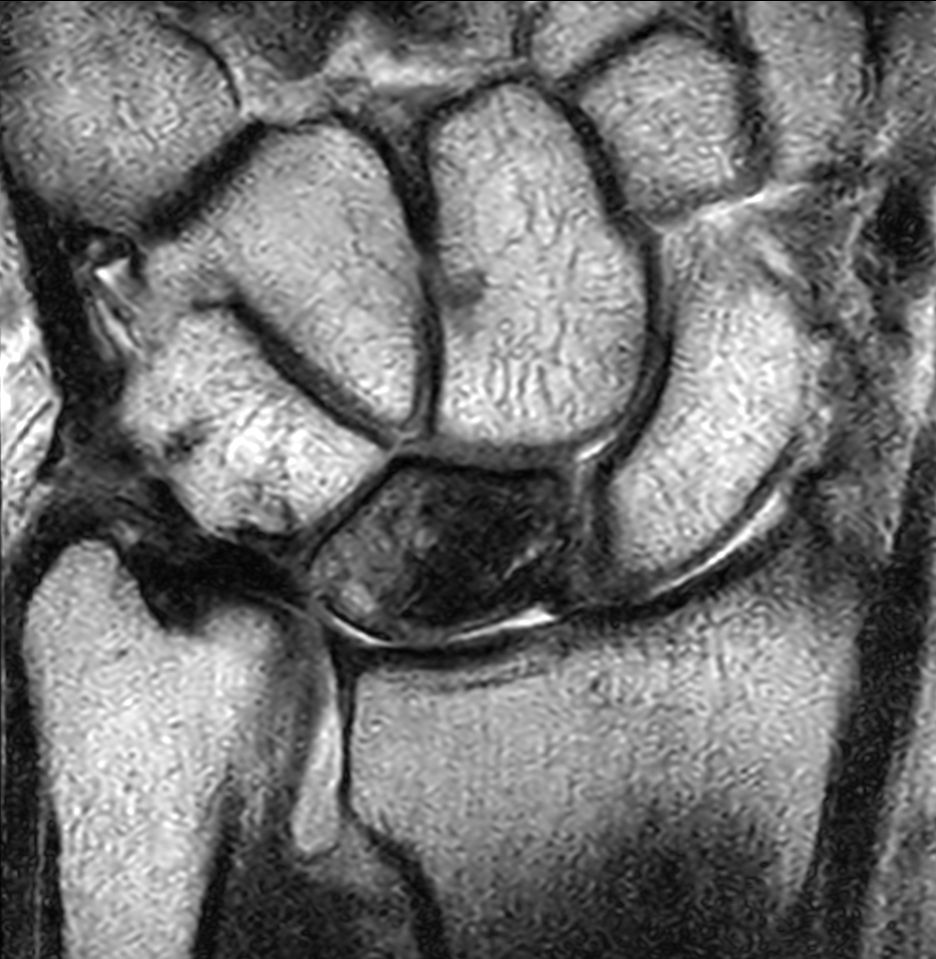

Patient with a lesion in his wrist. dS Microscopy coil set is used, consisting of two 47 mm coils, for small field-of-view imaging with high in-slice spatial resolution and a high signal-to-noise ratio. Compressed SENSE is used in all sequences to shorten the overall exam time for the patient.

Coronal T1w TSECompressed SENSE